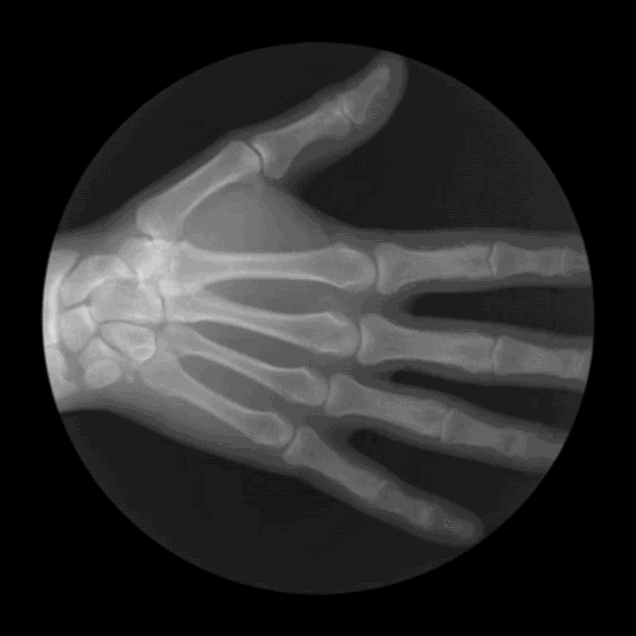

12. Занятный анимированный рентгеновский снимок

Графический дизайнер из Сан-Франциско Кэмерон Дрейк создает серии GIF-файлов на основе рентгеновских снимков.